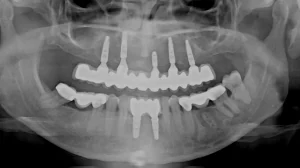

This patient was fed up with her denture and remaining loose upper teeth.

5 upper implants have been placed that support a bridge with 13 teeth in the top jaw.

This is a full arch porcelain bridge which the lady was delighted with.